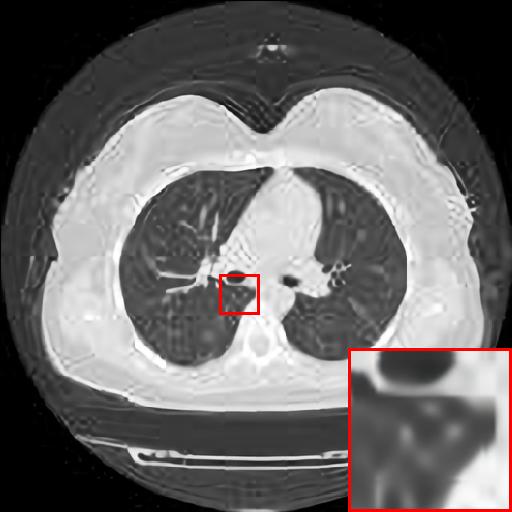

Refer to caption

(a) Original HD image

(b) Bicubic

(c) EDSR

(d) WDSR

(e) T-GAN

Figure 6: Reconstruction results of each algorithm for low-doze chest CT images.

In this section, we selected chest CT images of COVID-19 patients in an actual hospital [26] for our experiments. The visualization results of the experiments are shown in Figure 5 and Figure 6. The experimental results show that our proposed T-GAN is also applicable to the super-resolution reconstruction of low-dose CT images, and the high-resolution images obtained by our model have more detailed information compared with the baseline algorithm.